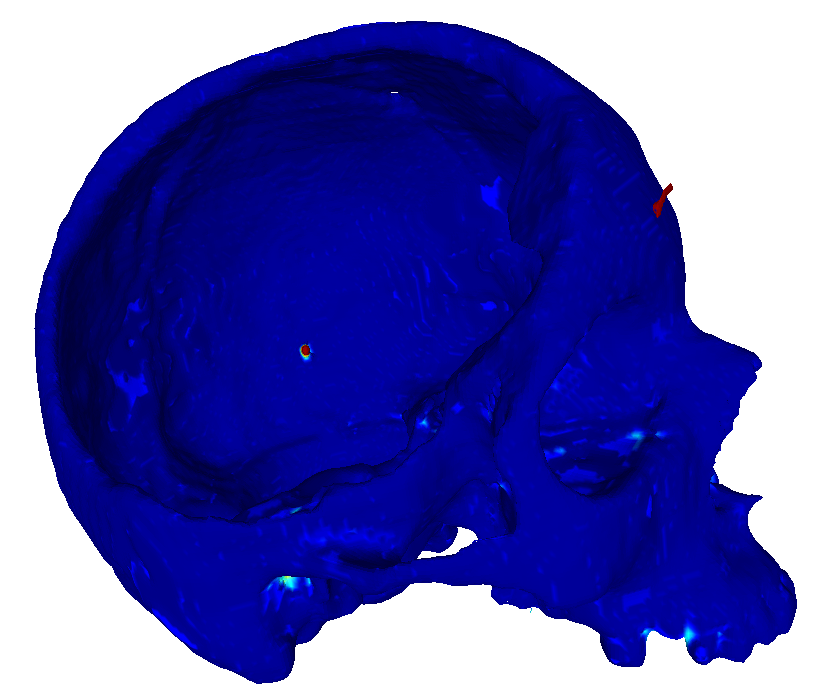

22 scans were randomly selected as test subjects for the experiment, leaving 177 skulls for model training. Using convolutional kernels of size 3 in all the CNN models results in the 3D model having the same number of trainable parameters as the sum of the three orthogonal 2D models. The comparison between the MV ensemble and the 3D approach can therefore be considered an ablation study to an extent. CutCNN models also have a similar number of parameters, the only difference being the final edge probability output layer. Quantitative comparison of results of each method are presented in Figure 4 and Table 1. Further qualitative results are shown in Figure 5 and 1.

CutCNN segmentation framework resulted in a performance gain in all cases in terms of every metric used in the experiment over standard CNN approaches. The output of CNN object probability map often contains errors near external objects or smaller tissue defects as these are scarce in the training data distribution. However, the graph-cut optimization guides the resulting binary segmentation towards a spatially consistent and compact shape, often eliminating these artifacts if a detected edge corresponds mostly to the correct object boundary. This effect is further illustrated in Fig. 1.

Our second observation is that using 3D convolutional kernels has a rather small effect on the final segmentation precision quantitatively compared to the MV approach. However, although the quantitative difference is small, for applications in medical additive manufacturing, it is important to avoid ragged segmentation output which may result from MV CNN in areas of lower model certainty. These include for example teeth, which are challenging to detect, especially when the lower and upper teeth are in contact (see Figure 5 a), or maxillary sinus, which is often enclosed in order to improve mechanical stability of the manufactured model (see Figure 5 b). Therefore, 3D U-nets are often considered necessary to avoid these discontinuities caused by slice-by-slice processing.